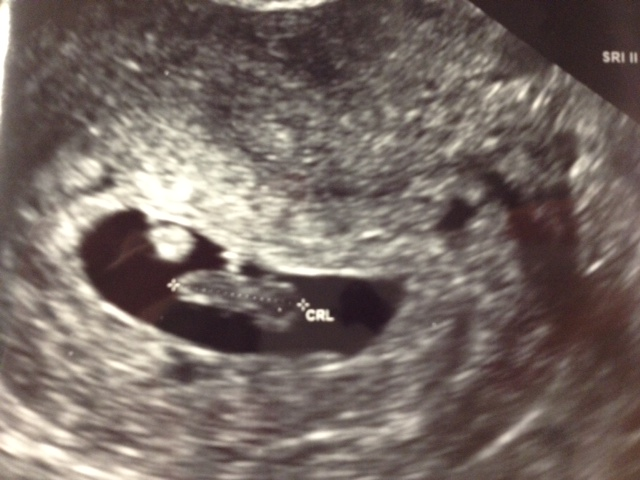

The heartbeat was 162 bpm! Up from the original 95 bpm at 6 weeks and the 125 bpm in the Emergency Room after the accident. I forgot how beautiful of a sound that fast beating heart is. This is my second pregnancy but I am still just as in awe of the fact that my body made that heart. My body made that heart beat. I won't be taking any of this pregnancy for granted. I will still mark every milestone with excitement and wonder and I will still write about everything I experience. I am even more exited to deliver this time since I know what an amazing experience it was the first time around. I wondered if I would ever get the chance to do this again.